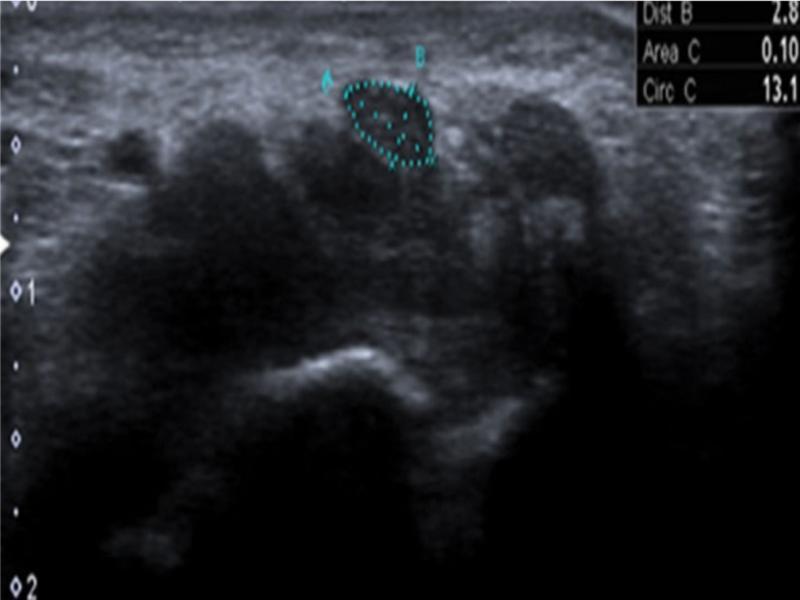

| CSA (cm2) | 0.11 (0.08,0.13) | 0.10 (0.08,0.13) | 0.11 |